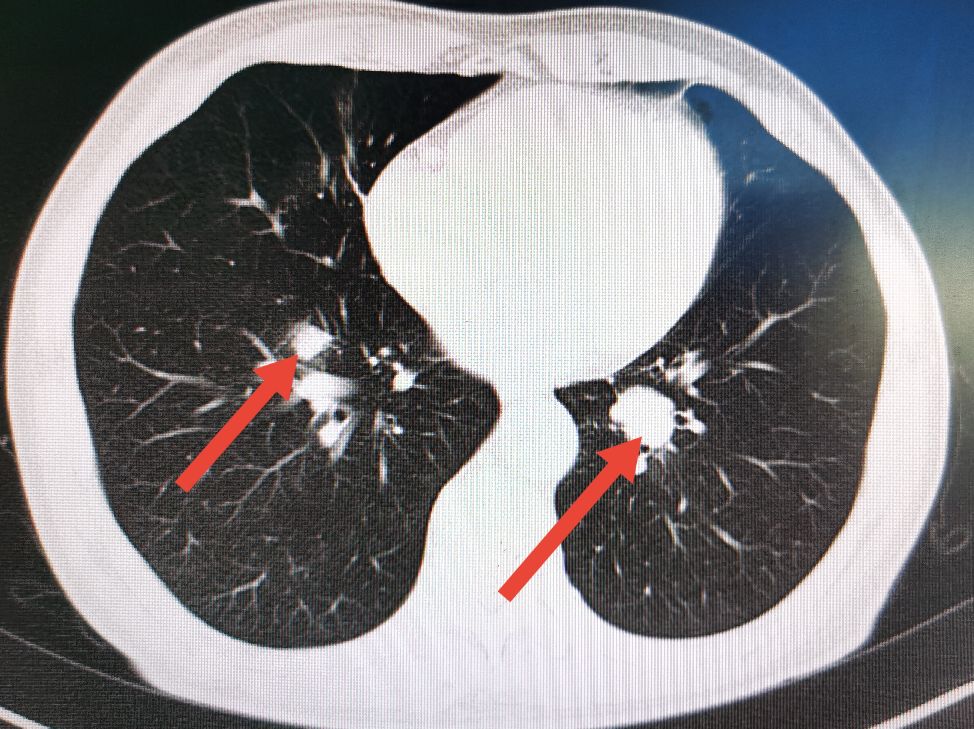

术后一年半的时候,常规复查时发现病人双肺出现明确的转移病灶,但患者一般情况及营养状况比术前有所好转,随后给予联合化疗和靶向药物治疗。

肺部CT显示左右肺均有转移病灶

经联合化疗及靶向药物治疗六个周期后,病人双肺的转移病灶完全消失,随后进行维持治疗至今没有发现新的转移病灶。

6个周期化疗及靶向药物治疗后转移病灶完全消失